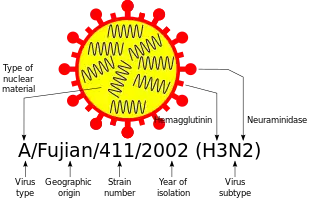

Influenzaviruses A, B, C, and D are very similar in overall structure.[8][56][57] The virus particle (also called the virion) is 80–120 nanometers in diameter such that the smallest virions adopt an elliptical shape.[58] The length of each particle varies considerably, owing to the fact that influenza is pleomorphic, and can be in excess of many tens of micrometers, producing filamentous virions.[59] However, despite these varied shapes, the viral particles of all influenza viruses are similar in composition.[60] These are made of a viral envelope containing the glycoproteins hemagglutinin and neuraminidase wrapped around a central core. The central core contains the viral RNA genome and other viral proteins that package and protect this RNA. RNA tends to be single stranded but in special cases it is double.[61] Unusually for a virus, its genome is not a single piece of nucleic acid; instead, it contains seven or eight pieces of segmented negative-sense RNA, each piece of RNA containing either one or two genes, which code for a gene product (protein).[60] For example, the influenza A genome contains 11 genes on eight pieces of RNA, encoding for 11 proteins: hemagglutinin (HA), neuraminidase (NA), nucleoprotein (NP), M1 (matrix 1 protein), M2, NS1 (non-structural protein 1), NS2 (other name is NEP, nuclear export protein), PA, PB1 (polymerase basic 1), PB1-F2 and PB2.[62]

Hemagglutinin (HA) and neuraminidase (NA) are the two large glycoproteins on the outside of the viral particles. HA is a lectin that mediates binding of the virus to target cells and entry of the viral genome into the target cell, while NA is involved in the release of progeny virus from infected cells, by cleaving sugars that bind the mature viral particles.[63] Thus, these proteins are targets for antiviral medications.[64] Furthermore, they are antigens to which antibodies can be raised. Influenza A viruses are classified into subtypes based on antibody responses to HA and NA. These different types of HA and NA form the basis of the H and N distinctions in, for example, H5N1.[65] There are 18 H and 11 N subtypes known, but only H 1, 2 and 3, and N 1 and 2 are commonly found in humans.[66][67]